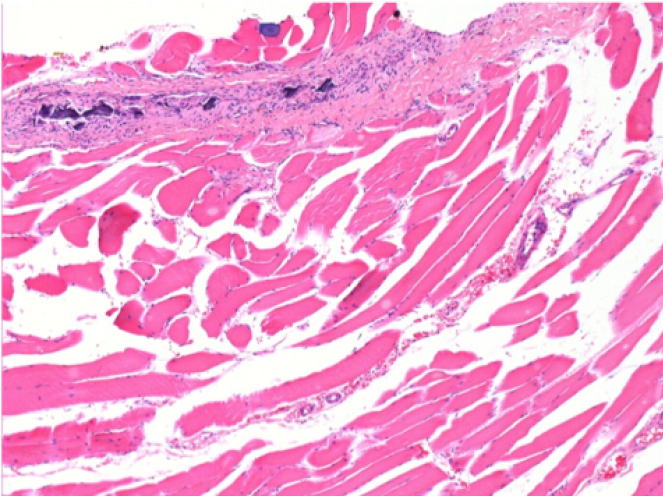

1 mese dopo Iniezione Endopeel

Scatola Nr 3

1 mese dopo Iniezione 0.1ml di Endopeel nel muscolo pretibiale destro ( Dx) .

Che cosa viene visualizzato in nero nella figura Sx : 100x-Giorno30 non é una necrosi come potrebbe immaginare un dilettante.

In effetti, 4 conclusioni devono essere prese in considerazione

- un artefatto di colorazione

- un`assenza di necrosi

- un`apoptosi

- un processo biorigenerativo

Sx : Controllo-100x-Giorno30

Dx:100x-Giorno30

Dx :400x-Giorno30